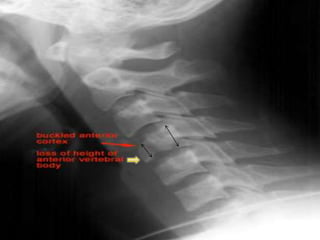

Flexion Teardrop Fracture C5-6

fracture is the result of a combination

of flexion and compression ,most commonly at C5-6

 The teardrop fragment comes from the

anteroinferior aspect of the vertebral body. The

larger posterior part of the vertebral body

is displaced backward into the spinal canal.

Best seen on lateral view

 It is an completely unstable fracture associated with

complete disruption of ligaments and anterior cord

syndrome and quadriplegia

 70% of patients have neurologic deficit.

common in MOTOR VECHICLE ACCIDENT

Signs:

Prevertebral swelling

associated with anterior

longitudinal ligament tear.

Teardrop fragment from

anterior vertebral body

avulsion fracture.

Posterior vertebral body

subluxation into the spinal

canal.

Spinal cord compression

from vertebral body

displacement.

Fracture of the spinous

process.